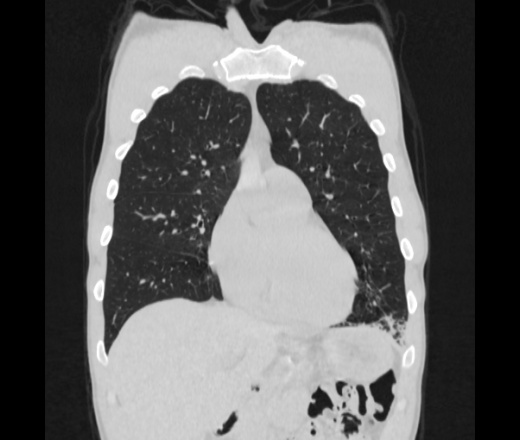

Мужчина пенсионного возраста. Цель назначения КТ ислючение зла в левом легком. Вижу тракционные бронхоэктазы с рубцовой эмфиземой по периферии, скорее всего БЭБ в стадии обострения. Дивертикулы трахеи. Выложил из за того что есть доля сомнения в отношении исключения зно3, немного смущают линии похожие на Керли.